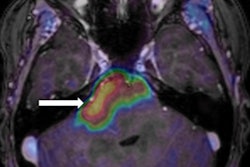

The analysis revealed a Kirsten rat sarcoma (KRAS) viral mutation in 96 patients (28%) and an epidermal growth factor receptor (EGFR) mutation in 44 patients (13%). The results indicate that EGFR mutations may drive different metabolic tumor phenotypes that are captured in PET images, while KRAS-mutated tumors do not.

FDG-PET shows patients with EGFR mutation, KRAS mutation, and EGFR-negative and KRAS-negative tumors. Stage I tumors (top) and stage III tumors (bottom) are shown, with arrows indicating the locations of the lung tumors. Image courtesy of Stephen S.F. Yip, PhD; Hugo Aerts, PhD; Dr. John Kim; and JNM.